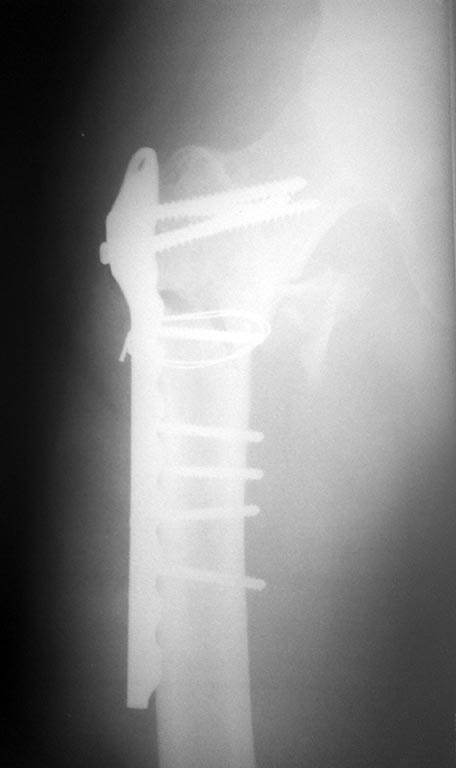

Имя     : 20160314120719.jpg